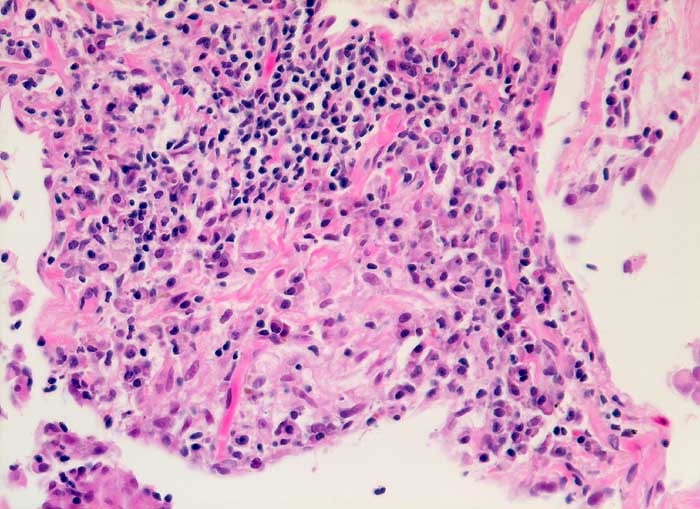

Die exogene allergische Alveolitis (Hypersensitivitätspneumonie) ist eine Entzündungsreaktion der Lunge, die bei prädisponierten Individuen durch pflanzliche oder tierische Inhalationsantigene ausgelöst werden kann. Die BAL Befunde hängen vom Stadium der Erkrankung ab. In der perakuten Phase überwiegen neutrophile Granulozyten. Ausserdem sind in den ersten Tagen der Exposition die Mastzellen auf über 1% erhöht (mehr als 3/10 HPF), um nach 1 bis 3 Monaten wieder auf Normalwerte abzufallen. Bei aktiver EAA besteht oft eine extreme Lymphozytose von 60-70%. Bei chronischer Erkrankung sind Schaumzellen, einige eosinophile Granulozyten und als Ausdruck der Fibrose reichlich neutrophile Granulozyten nachzuweisen. Eine Lymphozytose von mehr als 100x10^6/L in der BAL zusammmen mit einem erniedrigten HS Quotienten von unter 0.5 sind bei entsprechendem klinischen Verdacht vereinbar mit einer exogenen allergischen Alveolitis.